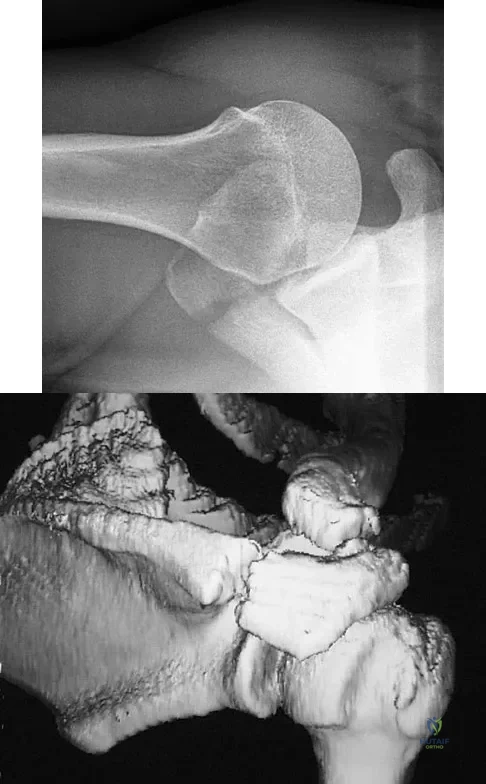

A 22-year-old right hand-dominant man who fell off his motorcycle onto the tip of his right shoulder 2 weeks ago now reports pain and difficulty raising his right arm. Examination reveals tenderness and gross movement over the lateral scapular spine and severe weakness during resisted abduction. A radiograph and 3D-CT scan are shown in Figures 24a and 24b. What is the next most appropriate step in management?

Explanation